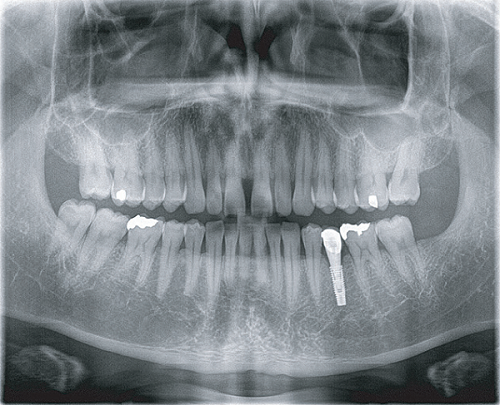

臨 床 圖 集